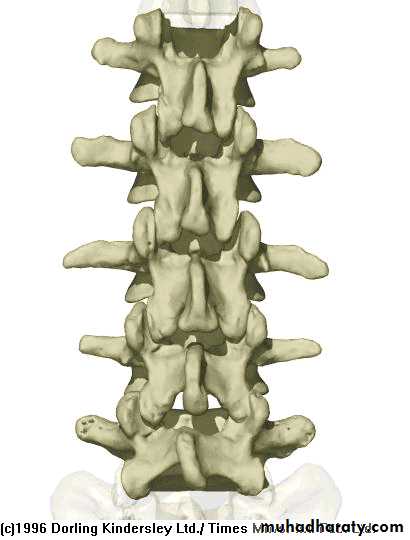

Lumbar Spine Anatomy

L1

L2

L5

L3

L4

Curvature is Lordotic

Facets are aligned vertically and allow bending

Vertebral body is kidney shaped in MRI